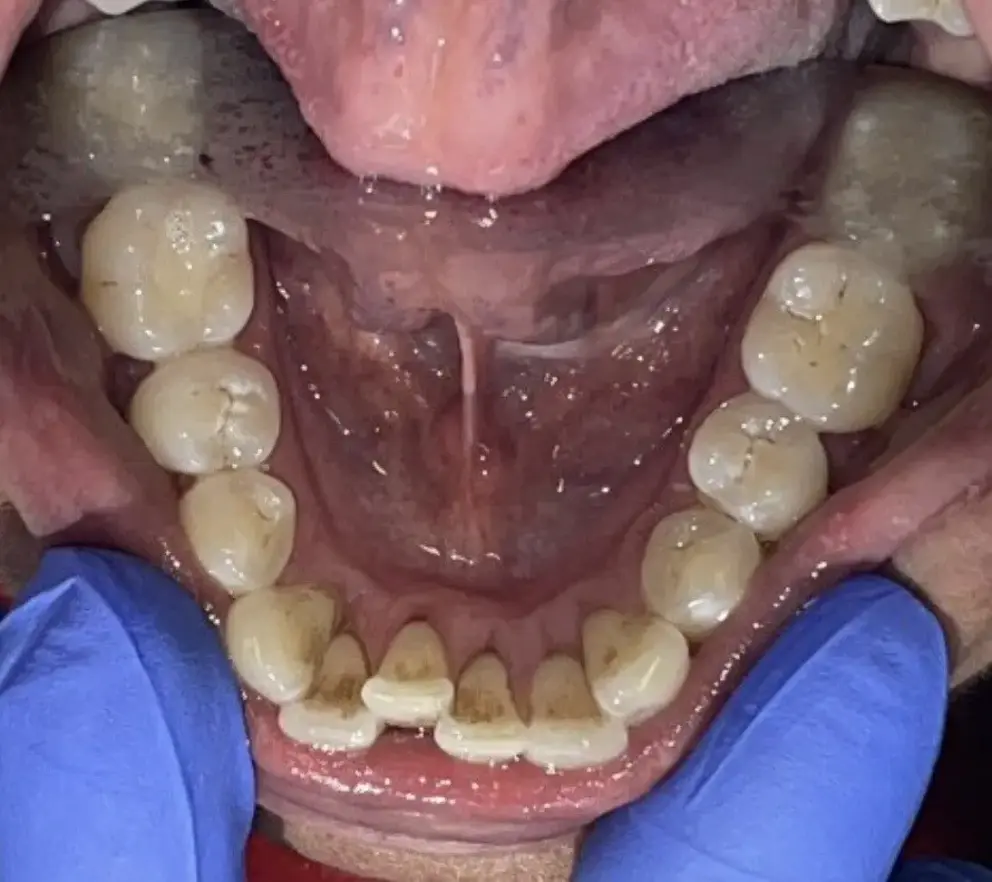

Vi tilbyder alle former for tandbehandlinger med speciale i både funktionelle og æstetiske løsninger som snorkeskinner, tandretning med Invisalign samt professionel udført tandblegning.